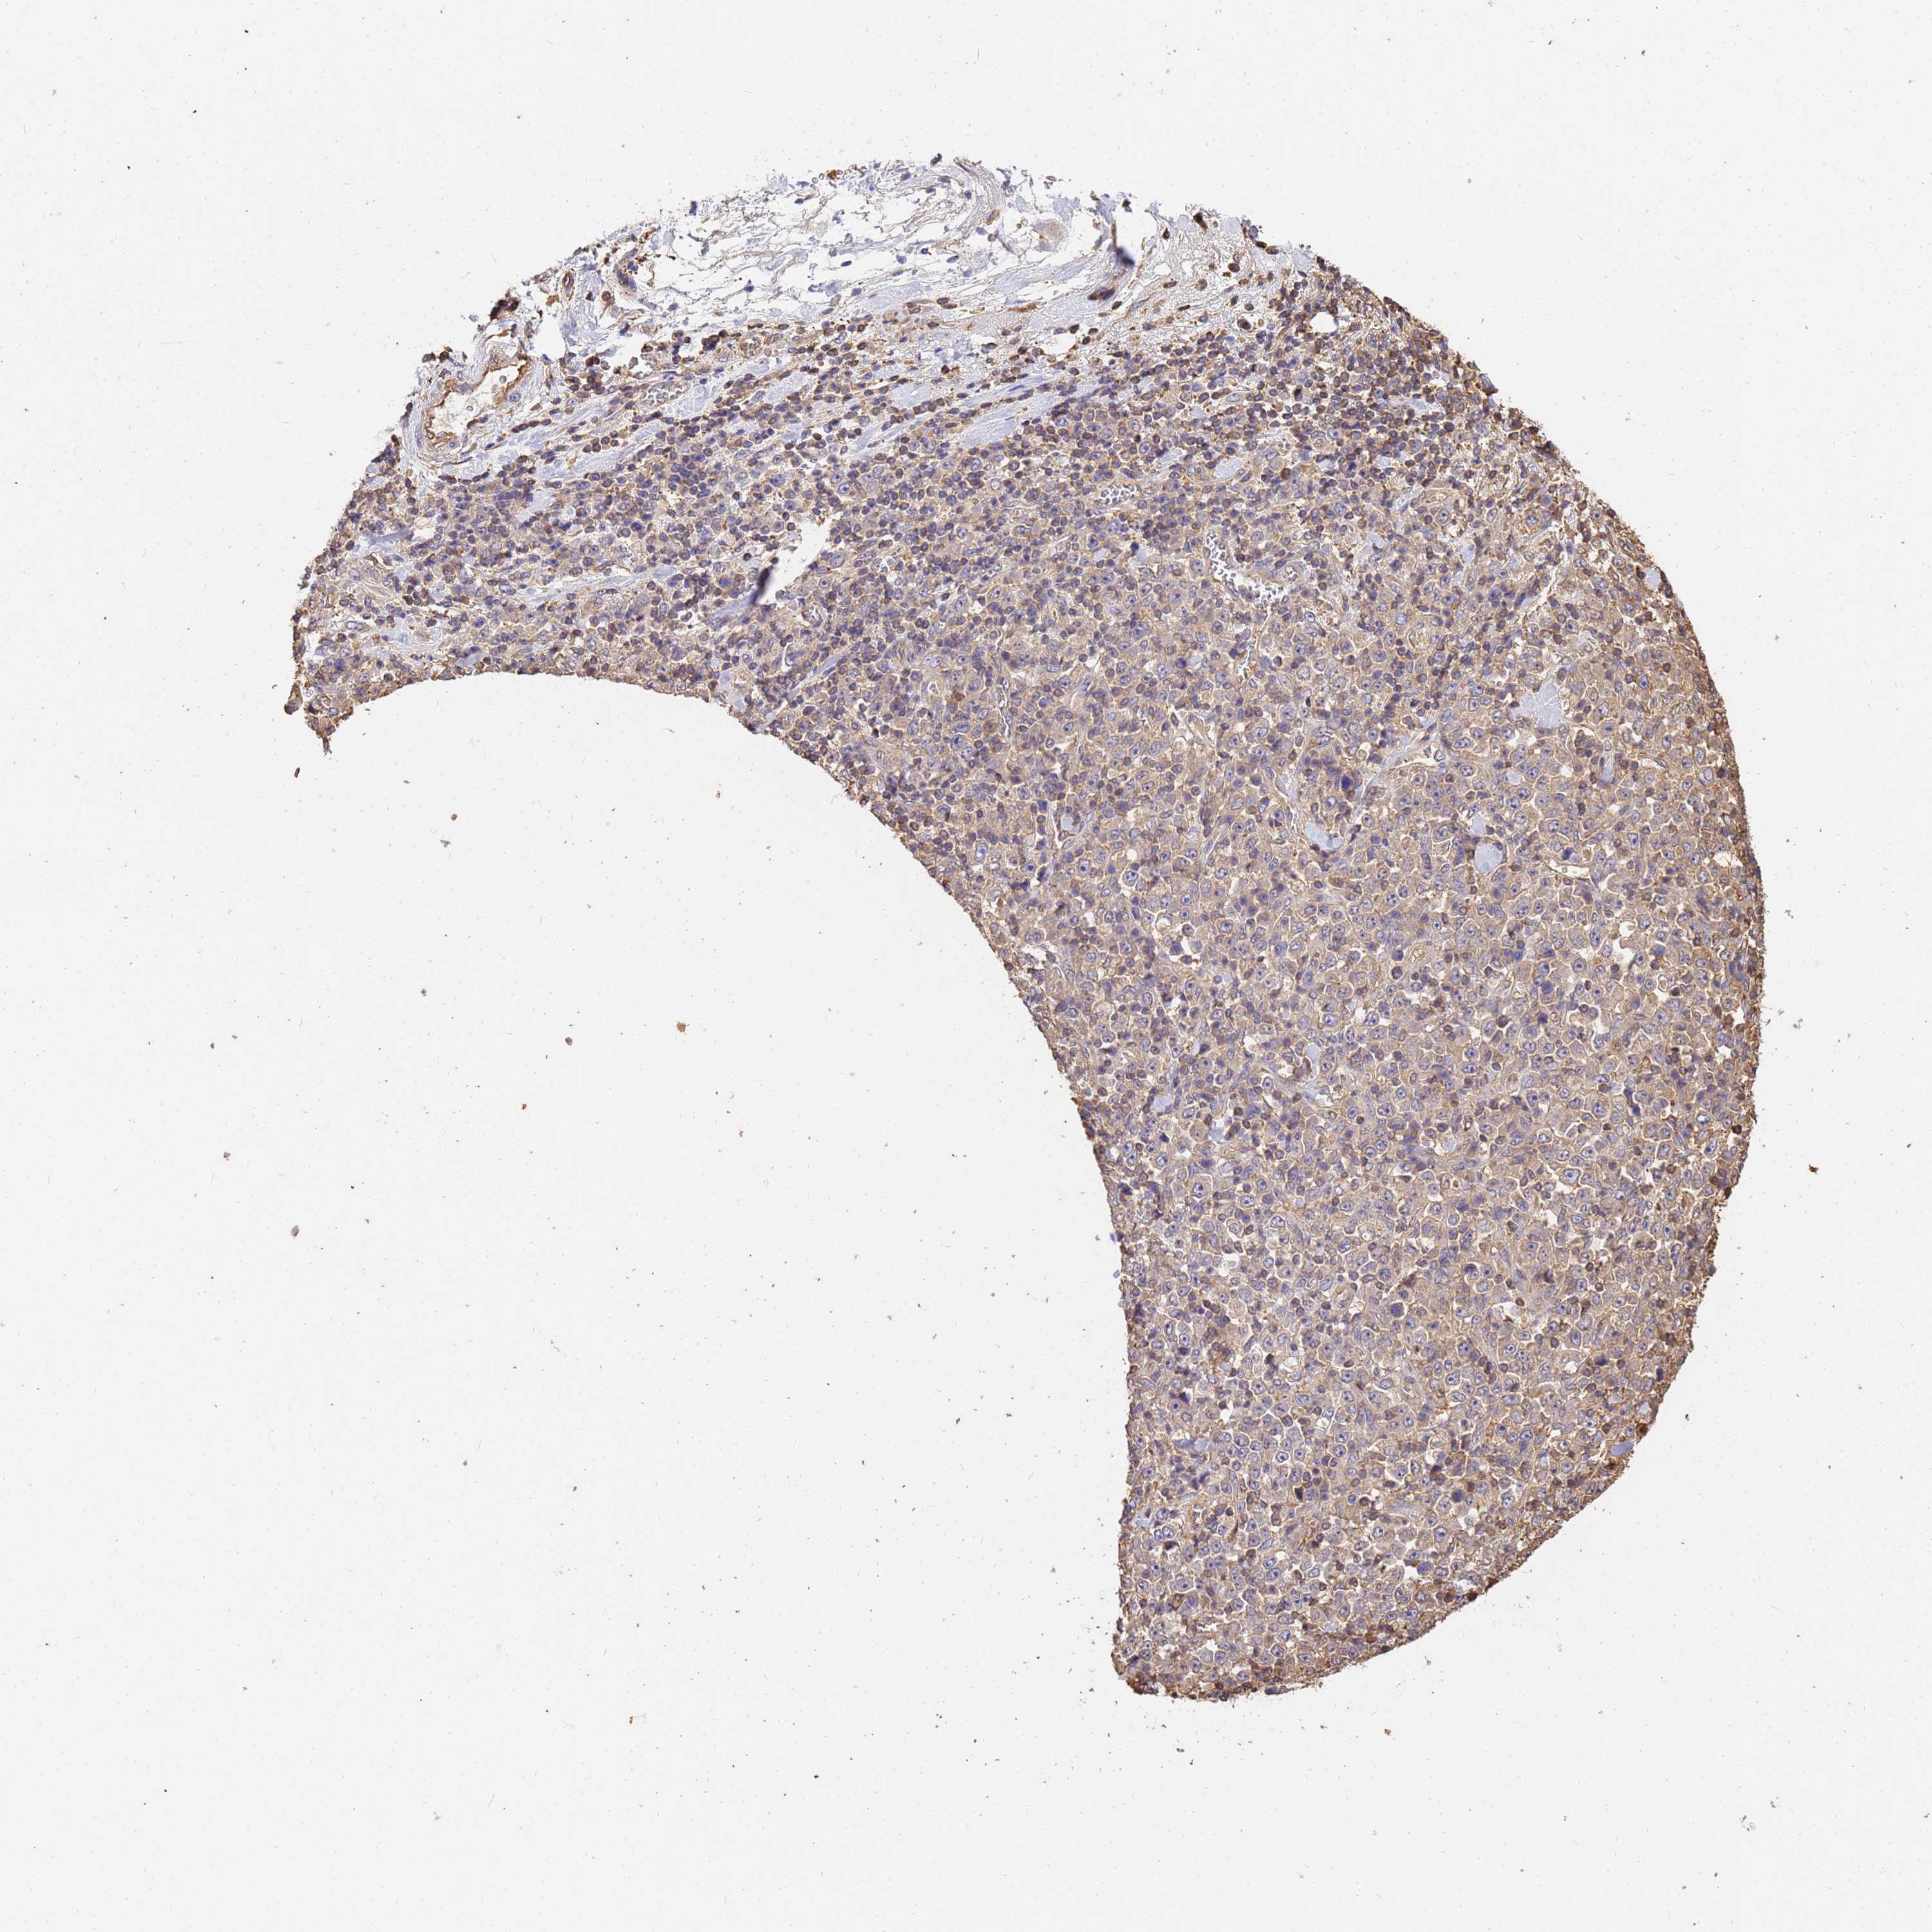

STOMACH CANCER - Protein expressioni

A mouse-over function shows sample information and annotation data. Click on an image to view it in a full screen mode. Samples can be filtered based on level of antibody staining by selecting one or several of the following categories: high, medium, low and not detected. The assay and annotation is described here.

Note that samples used for immunohistochemistry by the Human Protein Atlas do not correspond to samples in the TCGA dataset.

Antibody stainingi

Antibody staining in the annotated cell types in the current human tissue is reported as not detected, low, medium, or high, based on conventional immunohistochemistry profiling in selected tissues. This score is based on the combination of the staining intensity and fraction of stained cells.

Each image is clickable and will lead to virtual microscopy that enables deeper exploration of all samples and also displays staining intensity scores, fraction scores and subcellular localization as well as patient and tissue information for each sample.

Antibody HPA046186

Staining

High

Medium

Low

Not detected

Intensity

Strong

Moderate

Weak

Negative

Quantity

>75%

75%-25%

<25%

None

Location

Nuclear

Cytoplasmic/membranous

Cytoplasmic/membranous,nuclear

Adenocarcinoma, NOS